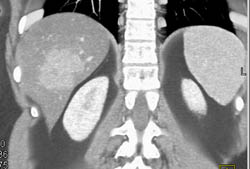

Cirrhosis With Varices